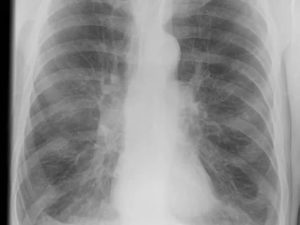

Рентгенограмма при пневмонии

Пневмония, или воспаление лёгких, отчётливо просматривается на рентгене. Правда, на начальной стадии могут возникнуть сложности. Вот что можно увидеть на снимке при воспалительном процессе:

- очаги воспаления в виде затенений различного размера;

- уровень поражения органа;

- воспалённую плевру и бронхиальное дерево;

- расширение корня лёгкого, как реакцию лимфатической системы на заболевание;

- усиление лёгочного рисунка.

Очаги воспаления могут иметь размеры до 1,5 см. Форма инфильтрата может быть любой. Размер поражённой области оценивается на фронтальном и боковом снимках.